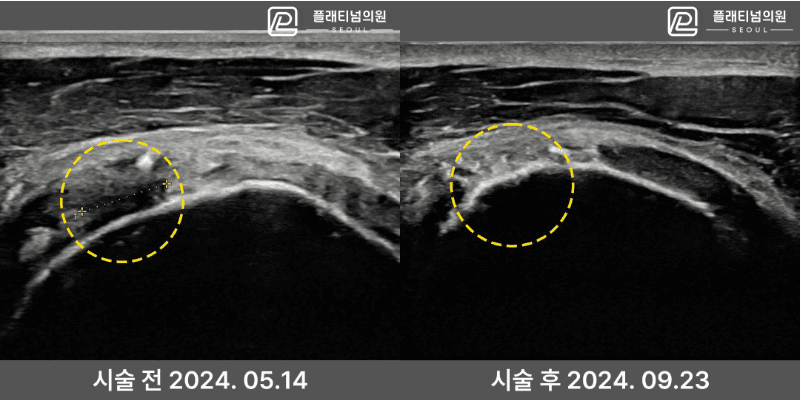

术前术后超声对比

实际患者超声对比。治疗前显示缺损的韧带组织在手术后可见恢复。

* 个人差异可能存在。不保证所有患者取得相同效果。